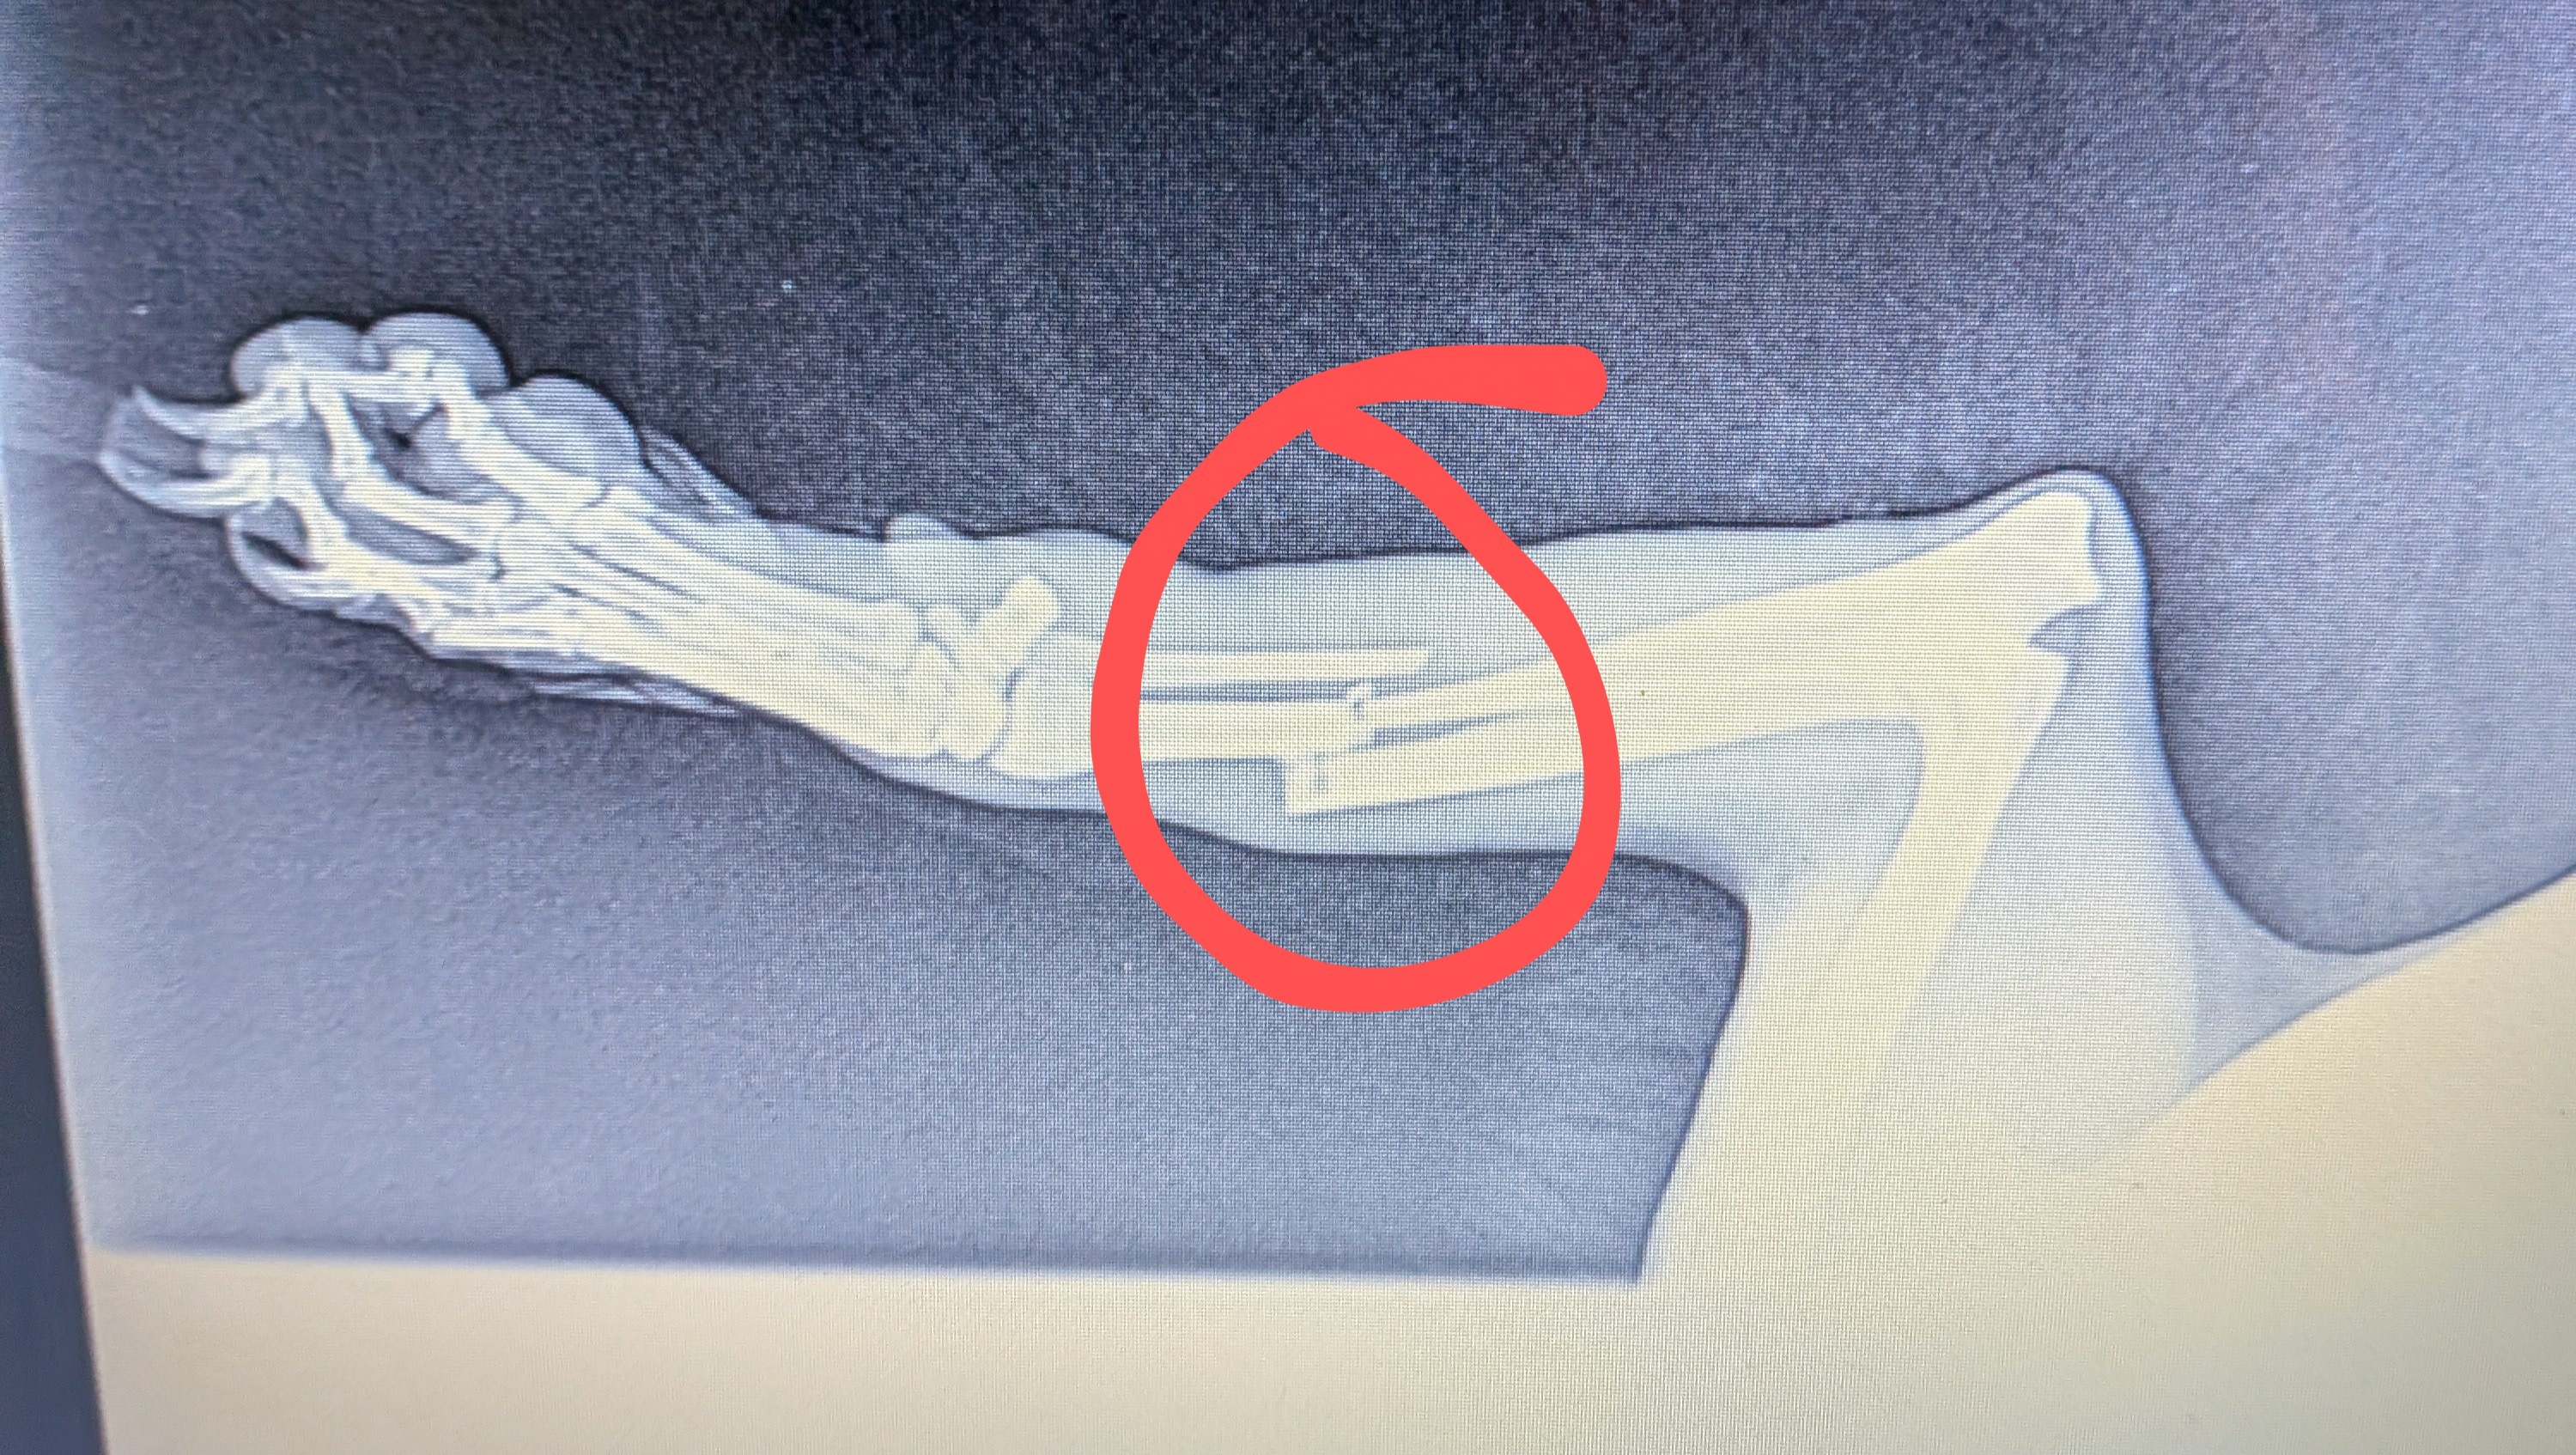

Hello, my name is Will. On Thursday, May 29th, while I was at work, I got a text from my daughter's grandma saying that when she came by to give Lady a treat, she noticed she was limping and thought that her leg was broken! So, immediately after I got off work, I rushed to see what was going on. Sure enough, Lady wasn't running up to me as she normally does. Her right front leg was completely limp, and she limped towards me in obvious pain. I inspected it as well as I could and knew then it was a break or a sprain. So, the next morning, I got a vet appointment for 1:30 to get her in and get X-rays done.

- Sure enough, it was a clean break. The veterinarian informed me that she would have to get surgery to have the bone placed right ASAP. Due to financial hardships recently, I just can't afford to get it done. So, I'm reaching out for any help possible. I've had Lady since she was 3 months old; she's 10 years old now. She's been the best dog anyone can ask for, and my kids absolutely love her! I've never done a GoFundMe or anything like this. I'm just in a bind right now and looking for any help I can get. Thank you.